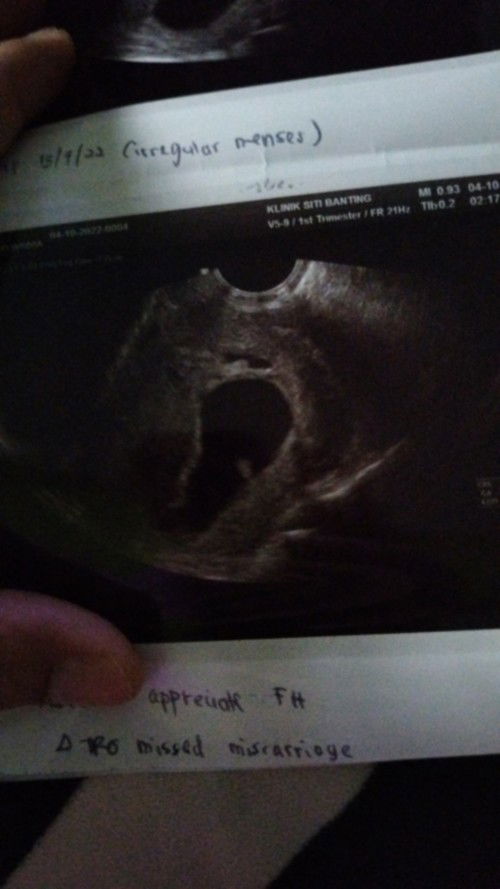

doc kata kemungkinan akan gugur dalam masa 2 minggu

semalam g scan tibe² keluar darah sikit pastu scan baby still 6 week lebih kalau ikut kantung 8 week lebih . doc ckp mcm tu terus tak comment apa². rasa sedih sgt . #pleasehelp #firstmom #firstbaby